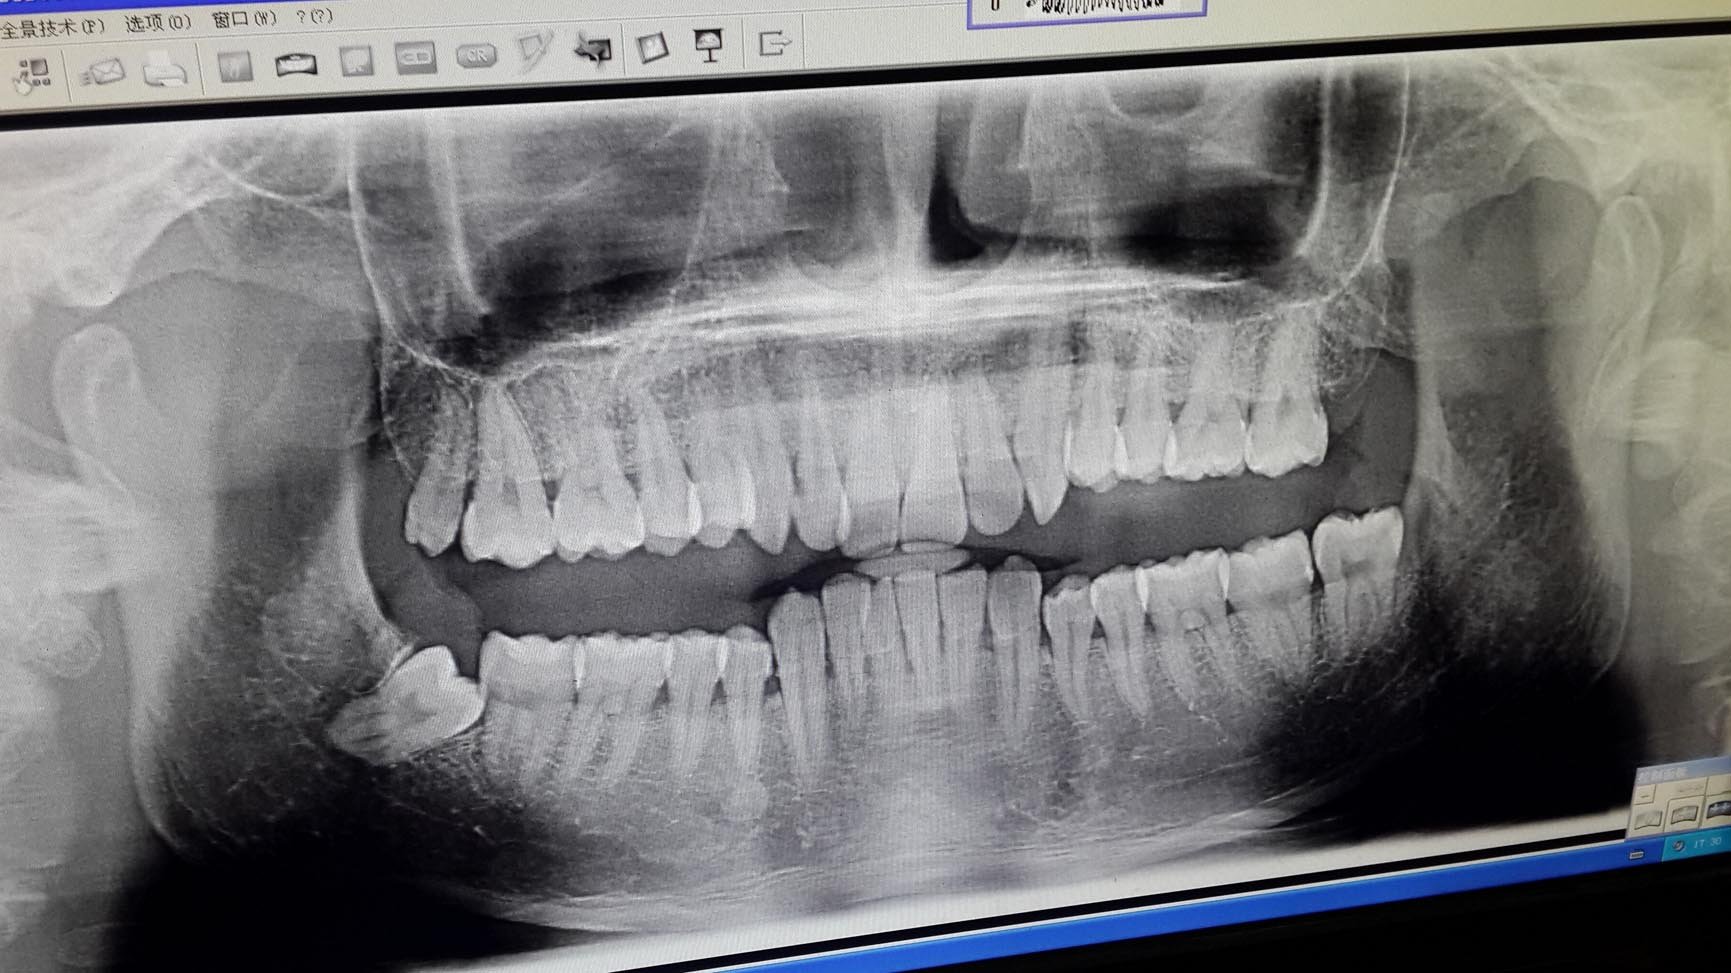

左下颚有颗智齿,痛过几次,发作的厉害的一次肿得不行,晚上睡觉都睡不着,疼得实在受不了,还发烧,最后是打点滴好的,痛的时候超想拔掉去,好了又没啥动力去了,小半年没发作过了,偶尔上火发作吃点下火的和消炎药就好了,这几个月感觉右下颚牙齿有点松动,咬起东西来发软,然后去牙科门诊检查,做了个全景X片,显示我右下颚有一颗隐藏的智齿在长出来,需要拔掉,这都没啥,最严重的是,居然说我前方一颗完整没事的牙齿根部有个球状物,说是肿瘤,需要拔除,然后还要栽牙,说一颗牙齿要6000-8000元,对我来说,这是万万没想到的事情,这颗牙平常没一点问题,我才30岁,还没结婚,现在就牙齿搞得这样,一点思想准备都没,现在把X片发上来,希望专业医生帮我看看具体要怎么弄,1.我这病是什么病?可不可以保守治疗,不拔牙齿?我这颗牙齿没问题2.右下颚的智齿肯定要拔,左下颚的呢?

一右下四也就是你问的那颗牙根尖部的病变我们叫牙骨质瘤又称根尖周牙骨质结构不良,或根尖周纤维结构不良。属于逝最北非肿瘤性骨瘤反应性增生。多见于青年人,女多见。常发生下颌前牙或双尖牙区。一般无自觉症状。也有发生神经压迫症状。x光片与根舞涉尖囊肿,根尖肉芽肿相似,牙髓活力测试可以鉴别。无症状时,无需处理,有神经症状或继发感染时,连同患牙一并摘除。 二、你的智典称齿劝您最好等炎症消下去后趁早拔除。最严重的右边的上下8一起拔除,左边的8您可以择期拔除因为它没有对颌牙会慢慢伸长。